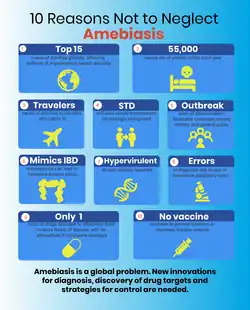

Amoebiasis is present all over the world,[7] though most cases occur in the developing world.[8] It is estimated that approximately 50 million people worldwide are infected with Entamoeba histolytica each year, with approximately 100,000 deaths among them.[3] The first case of amoebiasis was documented in 1875. In 1891, the disease was described in detail, resulting in the terms amoebic dysentery and amoebic liver abscess.[2] Further evidence from the Philippines in 1913 found that upon swallowing cysts of E. histolytica volunteers developed the disease.[2]

Most infected people, about 90%, are asymptomatic,[9] but this disease has the potential to become serious. It is estimated that about 40,000 to 100,000 people worldwide die annually due to amoebiasis.[5]

An estimated 500 million people worldwide are infected with Entamoeba, the majority of whom are infected with E. dispar and an estimated 10% are infected with E. histolytica.[25][3] Mortality from invasive E. histolytica infection is estimated at 100,000 per year.[3] Amoebiasis caused about 55,000 deaths worldwide in 2010, down from 68,000 in 1990.[26][27]

- ^ Shirley DT, Watanabe K, Moonah S (November 2019). "Significance of amebiasis: 10 reasons why neglecting amebiasis might come back to bite us in the gut". PLOS Neglected Tropical Diseases. 13 (11): e0007744. doi:10.1371/journal.pntd.0007744. PMC 6855409. PMID 31725715.